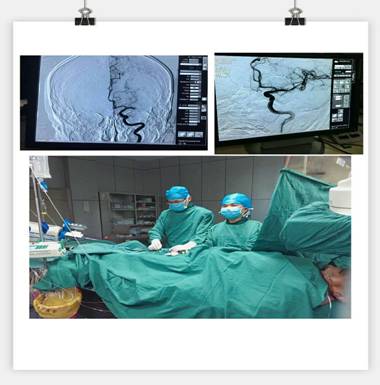

我院神經(jīng)內(nèi)科成功實(shí)施急性腦梗死靜脈溶栓聯(lián)合血管內(nèi)介入治療的橋接搶救

通訊員劉巧報(bào)道:10月21日,我院神經(jīng)內(nèi)科成功實(shí)施靜脈溶栓聯(lián)合血管內(nèi)介入治療的橋接搶救,成功救治了一位意識(shí)障礙的大面積腦梗塞的患者。

凌晨3點(diǎn)30分, “叮叮叮”一陣急促的電話響鈴打破了深夜的寧?kù)o。 “你好,這里是急診科,請(qǐng)準(zhǔn)備一張男床,腦血管意外患者”。患者是一名63歲男性,突發(fā)右側(cè)肢體乏力5.5小時(shí),由家屬用輪椅推送入院。入科后患者神志昏睡,心率48次/分,血壓186/100mmHg,NIHSS評(píng)分20分。病人情況十分危急,在劉禮泉主任指示下,患者為急性缺血性卒中,有溶栓指征。在劉主任與家屬談話期間,值班醫(yī)生同時(shí)開(kāi)出醫(yī)囑,患者予以硝普鈉控制血壓+尿激酶靜脈溶栓。夜班護(hù)士立即給病人抽血、吸氧、心電監(jiān)護(hù)、建立靜脈通道、準(zhǔn)備藥物……我們忙而不亂,默契配合。溶栓過(guò)程中劉主任一直守護(hù)在病人身旁,隨時(shí)觀察病人的病情變化。溶栓后,患者右側(cè)肢體有自主活動(dòng),但乏力癥狀及意識(shí)障礙無(wú)明顯緩解,劉主任立即決定行頭頸聯(lián)合CTA,明確是否有大血管閉塞。果不其然,患者頭部CTA提示左側(cè)大腦中動(dòng)脈M1段栓塞,如果大血管得不到及時(shí)開(kāi)通,必然會(huì)出現(xiàn)災(zāi)難性的后果。劉主任建議家屬考慮是否行血管內(nèi)治療開(kāi)通血管,經(jīng)過(guò)耐心細(xì)致的溝通,患者家屬同意行急診腦血管造影檢查及血管內(nèi)治療。 同時(shí)立即召集曾比賢副主任、聶利珞副主任趕來(lái)醫(yī)院,為患者在局麻下行全腦血管造影+顱內(nèi)血管取栓術(shù)。時(shí)間伴隨著沉悶緊張的氣氛一分一秒地過(guò)去,取栓的生命通道終于打開(kāi),患者病變血管恢復(fù)良好,手術(shù)圓滿成功,此時(shí)灰暗的天才微微光亮……

在急性腦梗死患者緊急救治中,時(shí)間就是生命,該病例運(yùn)用了動(dòng)靜脈聯(lián)合的方式治療急性腦梗塞,有效地保護(hù)了患者的大腦,此類(lèi)技術(shù)在國(guó)內(nèi)處于領(lǐng)先治療手段,溶栓、取栓同步進(jìn)行的橋接搶救措施起到了至關(guān)重要的作用。該病例成功取栓意味著我院神經(jīng)內(nèi)科在治療急性腦血管病方面已經(jīng)從傳統(tǒng)的靜脈溶栓向介入取栓的現(xiàn)代化治療方式轉(zhuǎn)變。